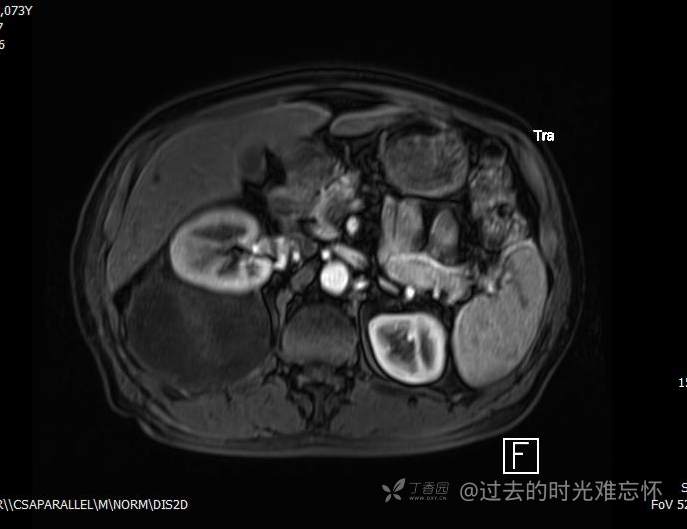

患者性别:男

患者年龄:73岁

主诉:咳嗽1月余。曾有血尿一次。后背部酸痛不适1-2年左右,无明显消瘦。

辅助检查:CT MRI

临床诊断:占位

治疗经过:手术

增强